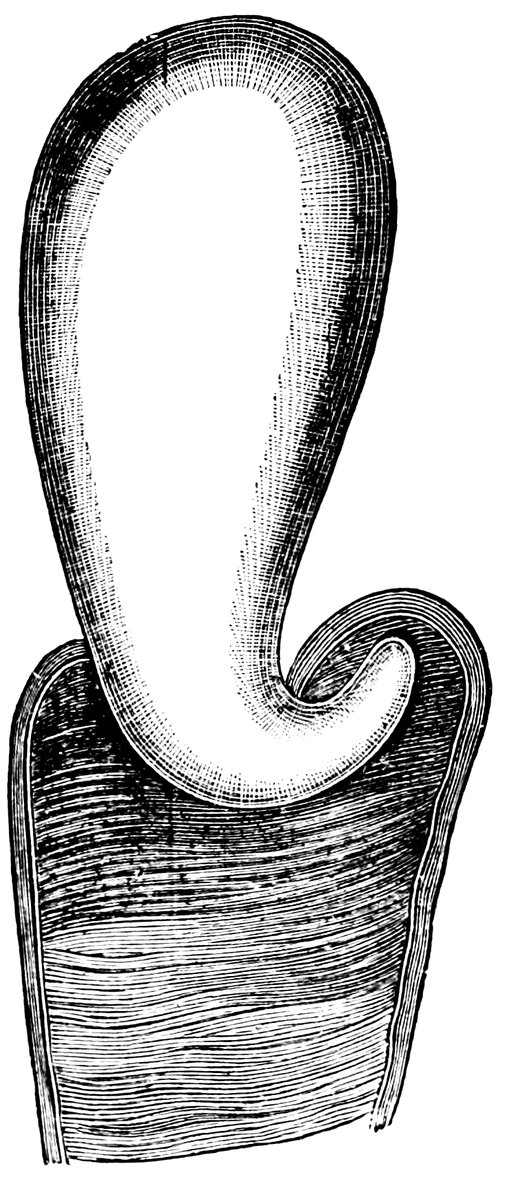

| x43. | Hymen with larger anterior and smaller posterior Apertures | 71 |